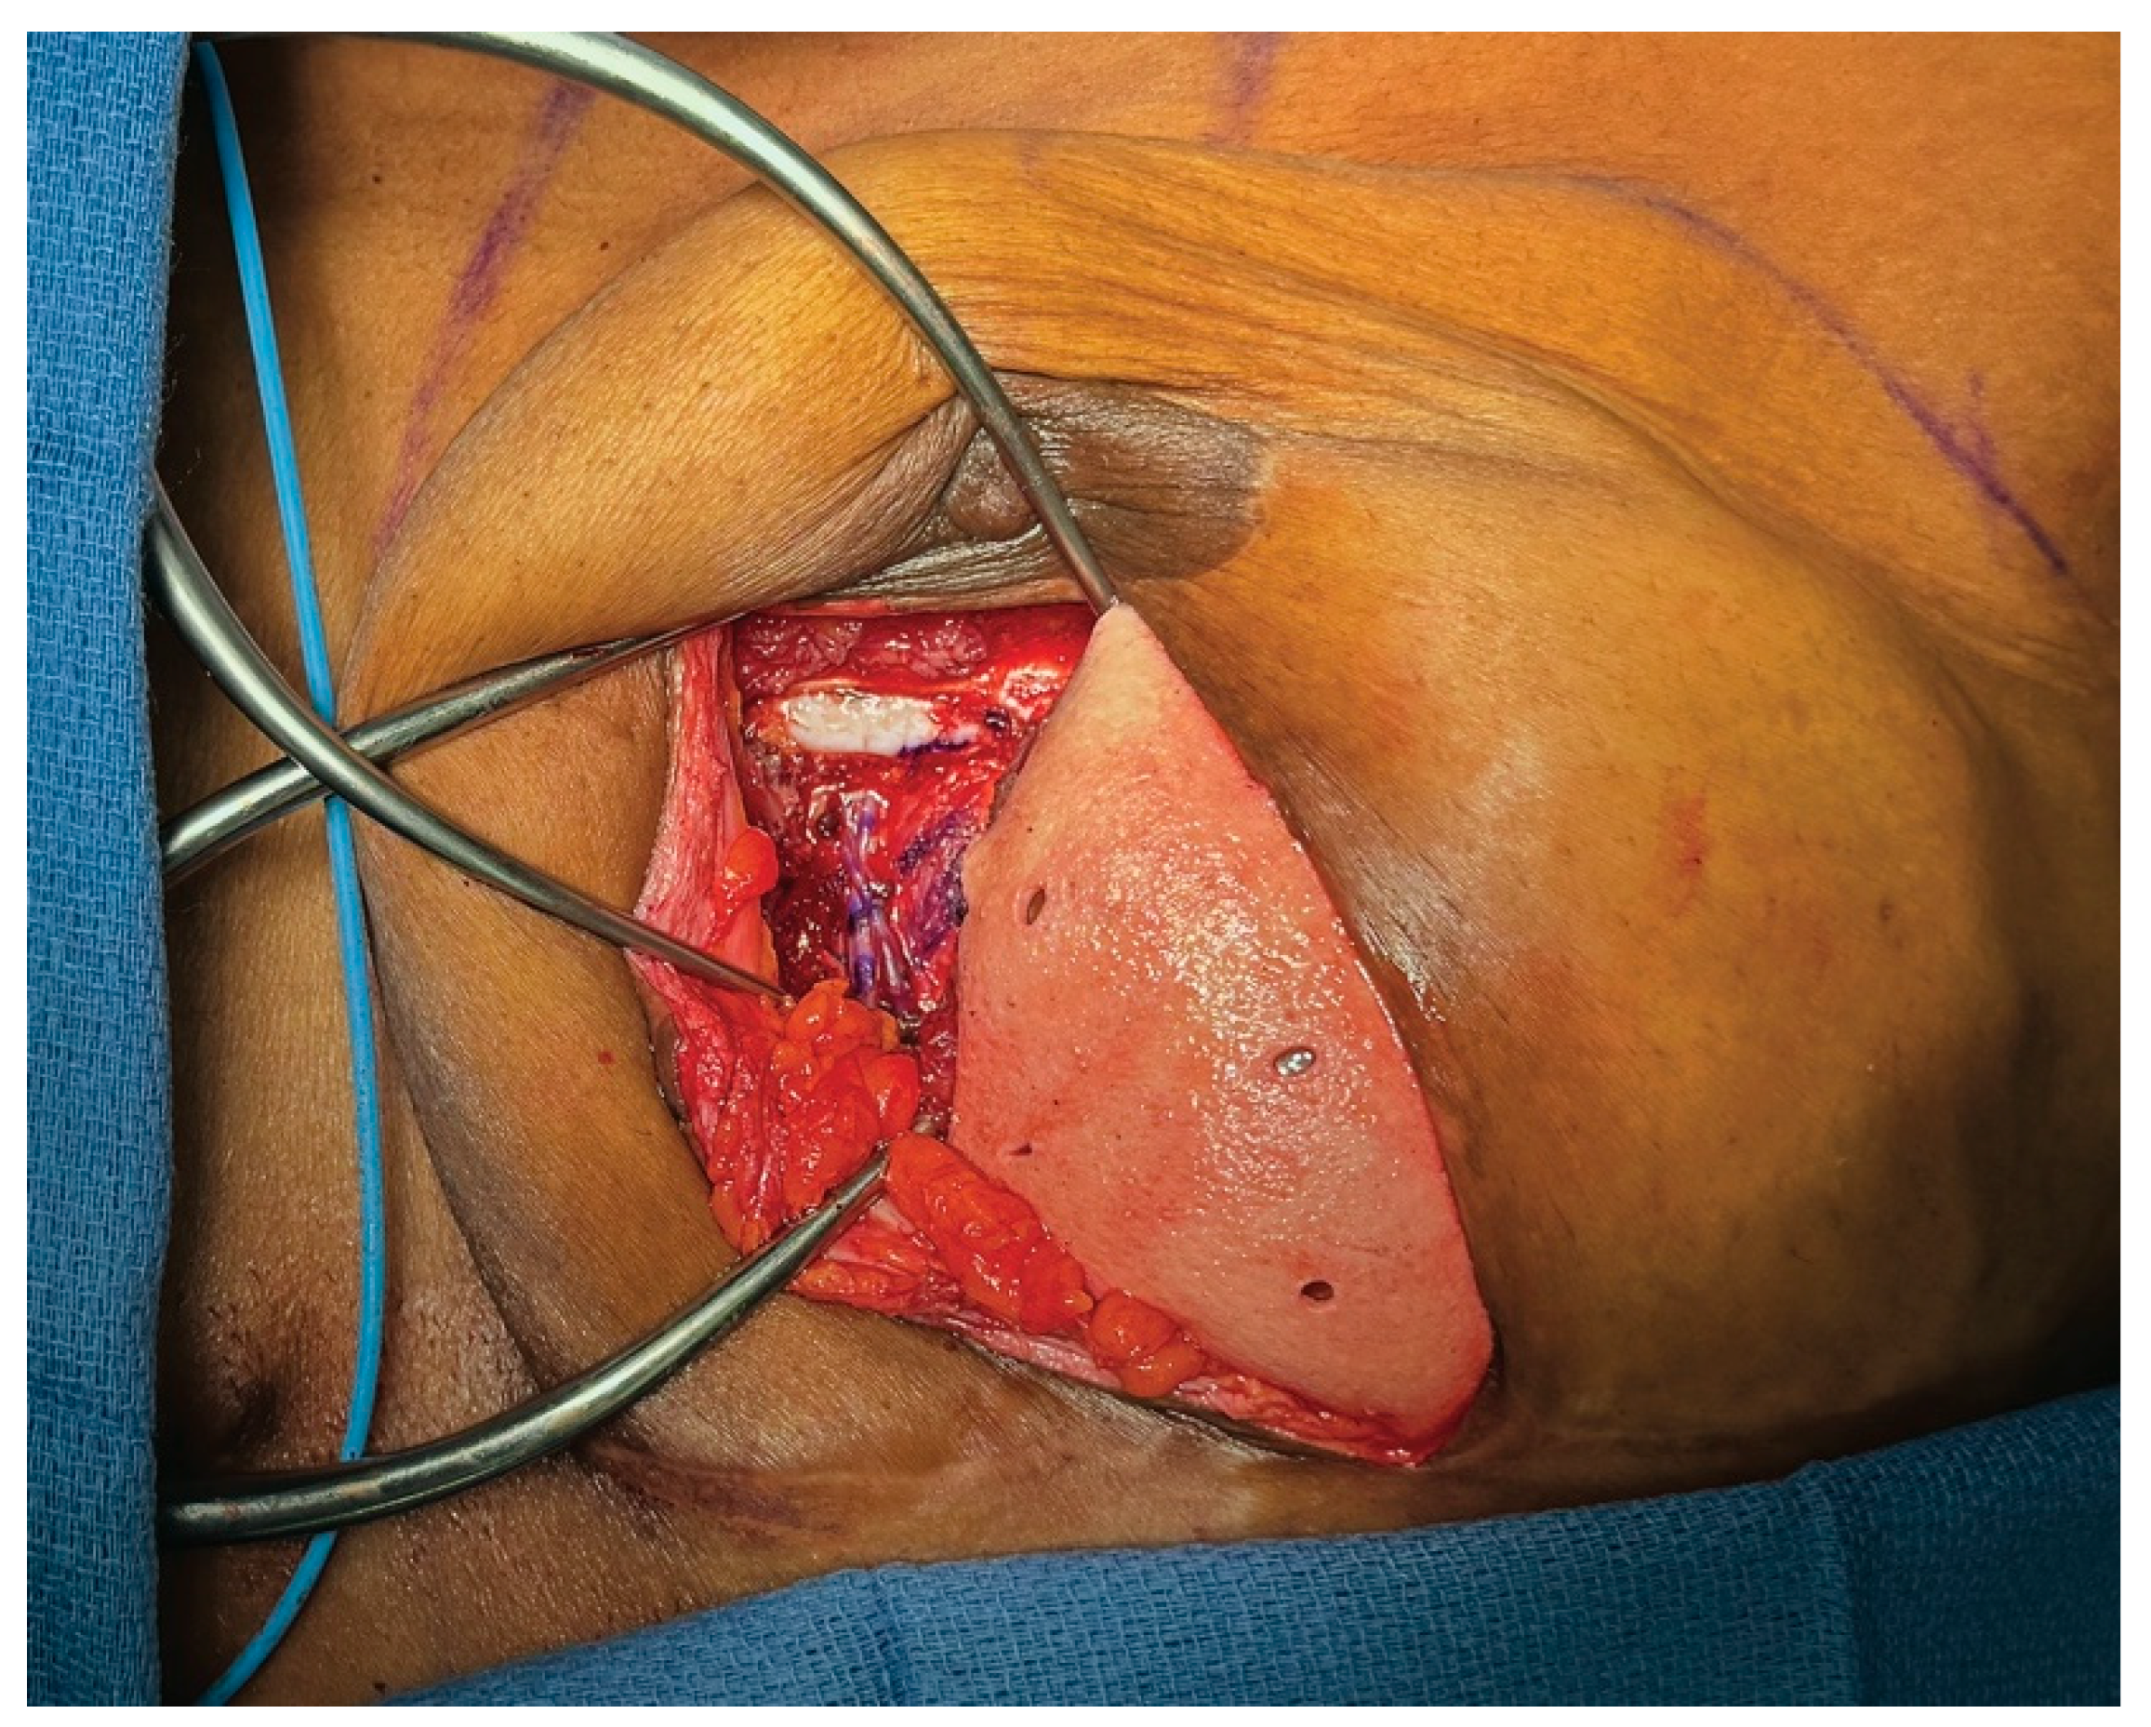

3.3. Case 1—HyFIL®

3.4. Operative Technique